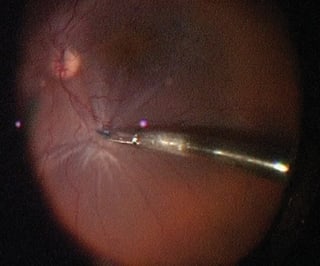

Eyes with proliferative vitreoretinopathy often have surface ERMs that may not be visible, especially on the surface of detached retina. Staining with Membrane Blue makes these peripheral ERMs and starfolds clearly visible and amenable to removal (Figure 2). The more complete the ERM removal, the greater the chance of long-term retinal reattachment in proliferative vitreoretinopathy surgery.

Figure 2. Stained epiretinal membrane at the apex of a retinal starfold grasped with intraocular forceps.